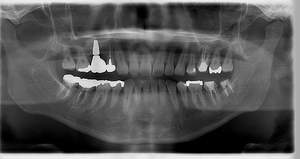

インプラント治療の症例2

レントゲン写真

- Befor

- After

| 年齢 | 50代・男性 |

|---|---|

| 主訴 | 左上7番 左下5番7番 |

| 治療内容 | ・インプラント埋入 ※1:GBR(骨造成)・・・骨再生誘導法。骨の高さや厚みを人工骨や人工膜などを使用し再生する方法 |

| 治療費 | 合計:1,809,500円(税込) ■内訳 ・左上7番 ・左下5番7番 |

| 治療期間 | 左上7番約1年 左下5番7番約10ヵ月 |

| 治療方針 | 左上7番は昔他院で被せものをしており、被せものの中が歯ぐきの中まで虫歯になっていたため抜歯せざるを得ない状態だった。抜歯と同時に骨造成を行い、骨が出来るまで4ヵ月待ってからインプラントを埋入した。 ※2ポンティック・・・歯のない部分を補うダミーの歯。 |

| 担当者所見 | 元々金属の被せものが多く入っていたため、2次カリエス※3が多かった。今回は金属ではなく、ジルコニアを使用し、2次カリエスにならないよう、患者様にはブラッシング指導とメンテナンスの重要性をお伝えした。 ※3二次カリエス・・・詰め物や被せものを入れた歯が虫歯になること。 |